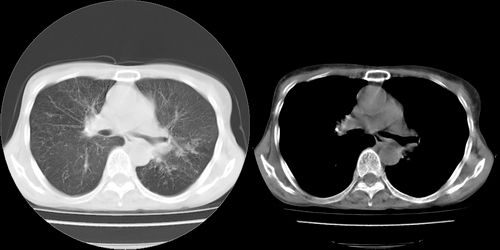

以下是引用lihuuuu在2006-7-18 18:16:00的发言:[br]支持肺结核诊断[br]本病例符合结核“三多”“三少”特征(多病灶、多形态、多钙化、少肿块、少堆积、少增强)中的前五个特征,另外左下叶背段有不张样改变-考虑伴有支气管内膜结核所致段不张。

以下是引用yang4132在2006-7-18 10:04:00的发言:[br]两肺多发 多形态病变,部分半纤维条索和斑点壮钙化,胸膜肥厚粘连,考虑结核。